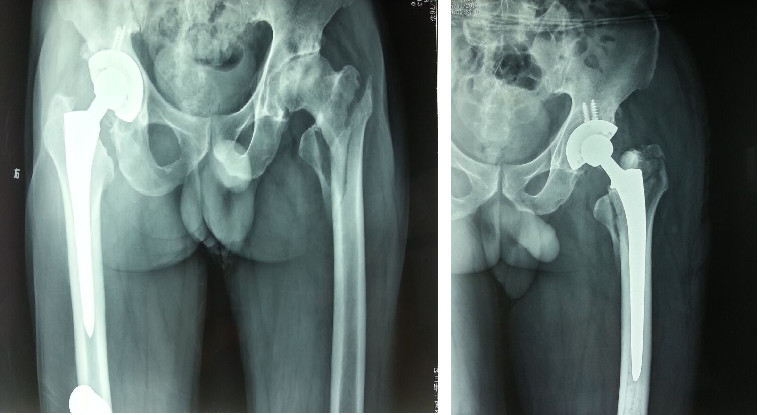

Âge supérieur à 80 ans.

Fracture intertrochantérienne comminutive et instable.

L'ostéoporose osseuse est évidente et la fixation interne est difficile à fixer efficacement.

Aucune limitation significative des mouvements de la hanche ou du genou avant la blessure.

L'état du corps entier peut tolérer le traitement chirurgical.

Les patients qui ne peuvent pas être traités au lit pendant une longue période.

Avantages : positionnement post-opératoire précoce au sol.Évitez les complications alitées.Prolonger le temps de survie et améliorer la qualité de vie.